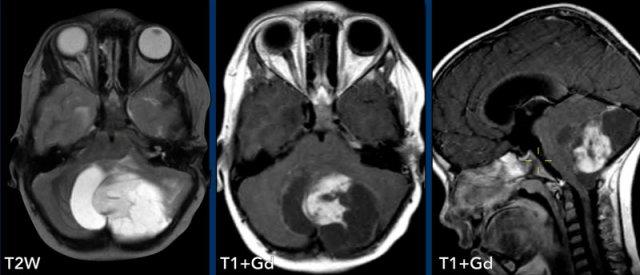

Các hình ảnh này của một trẻ 9 tuổi nhập viện vì đau đầu.

Hình ảnh

Có một khối nang lớn ở hố sau gây chèn ép và tắc nghẽn não thất bốn và thân não.

Ghi nhận một nốt đặc ngấm thuốc tương phản, cùng với sự ngấm thuốc của thành nang.

Kết luận

Chẩn đoán có khả năng nhất ở độ tuổi này là u nguyên bào thần kinh đệm lông.